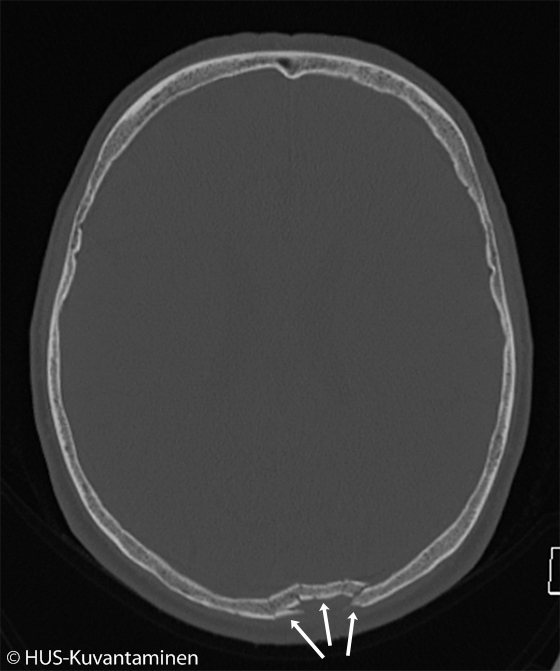

Kallonmurtuma pään TT-kuvassa (kuva 1 löydösmerkinnöin),

Luuikkunalla otetussa pään TT:ssä näkyy impressiomurtuma (nuolet) takana parietaaliluussa, mutta potilaalla ei todettu aivovauriota (ks. myös kuva «Kallonmurtuma pään TT-kuvassa»1

).Kuva: HUS-Kuvantaminen